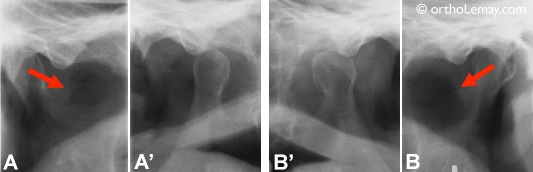

La radiographie tomographique “conventionnelle” permet d’évaluer la fonction des articulations

La radiographie tomographique “conventionnelle” permet d’évaluer la fonction des articulations. (A et B) Condyles de la mandibule lorsque la bouche est fermée. (A’ et B’) Lorsque la bouche est ouverte, on peut évaluer le déplacement des condyles vers l’avant (flèches). Il n’est cependant pas possible de visualiser les tissus mous sur une telle radiographie.